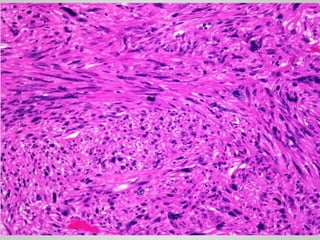

• Monophasic synovial sarcoma

• Uniform spindle cells with scant cytoplasm and dense chromatin

growing in short, tightly packed fascicles

Monophasic synovial sarcoma

SYNOVIAL SARCOMA • Misnomer •10% of all soft tissue sarcomas • 20s to 40s age • Deep-seated mass • t(x;18)(p11;q11) • Monophasic synovial sarcoma • Uniform spindle cells with scant cytoplasm and dense chromatin growing in short, tightly packed fascicles • Biphasic synovial sarcoma • Spindle cell component + gland-like structures • Epithelial markers (e.g., keratins)